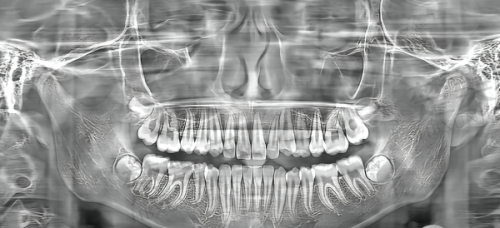

恒伦口腔医疗集团那可是大有来头,它的前身是山西红十字口腔医院,早在1956年就成立了,历史底蕴相当深厚。忻州分院是2016年开的,一进来就能感觉到这医院的实力不一般。它配备了好多海内外领跑的牙科诊疗设备,就比如说那个CRANEX3D口腔X射线计算机体层摄影系统,有了它,医生能更清楚地看到牙齿的情况,治疗起来也更精细。而且啊,这里的医护团队都是资历比较深的医师,经验那叫一个丰富。他们还和海内外有名的公司合作,像Nobel、ITI这些,开展新型的种植牙、牙齿矫正和根管治疗技术。不管你是想种牙、矫正牙齿,还是做根管治疗,在这里都能享受到良好的技术服务。